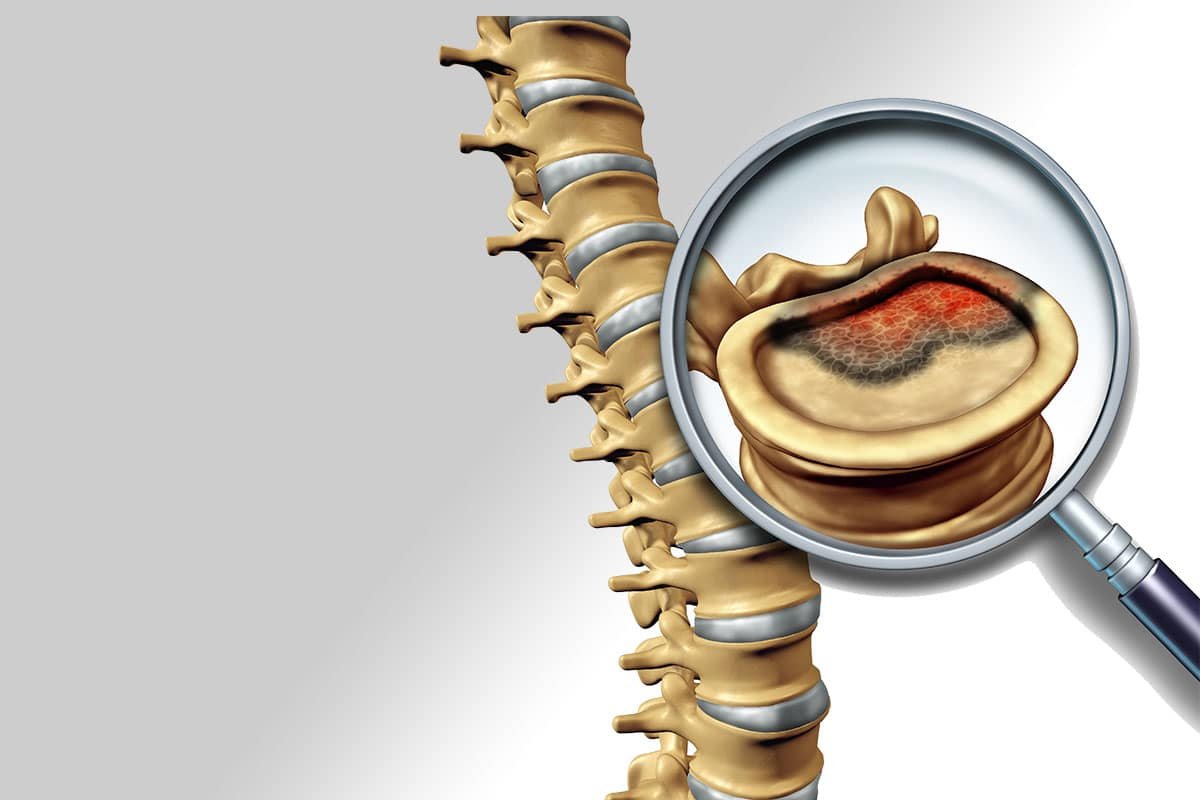

Osteoporosis and Vertebral Compression

Older patients and those with osteoporosis have a high risk of spinal fractures, particularly vertebral compression fractures. The main reason being low bone mass and strength, as well as an increased risk of falling. In these patients, vertebral compression fractures can occur during simple activities of daily living, such as coughing, sitting down quickly, or taking a step wrong.

As with many osteoporotic fractures, compression fractures are more common in women than men; however, the consequences are severe in both. Patients may experience acute and chronic pain, kyphotic deformity (increased forward curve of the spine), decreased quality of life, increased anxiety, depression, and death. Our geriatric doctors and nurses are involved in their care.